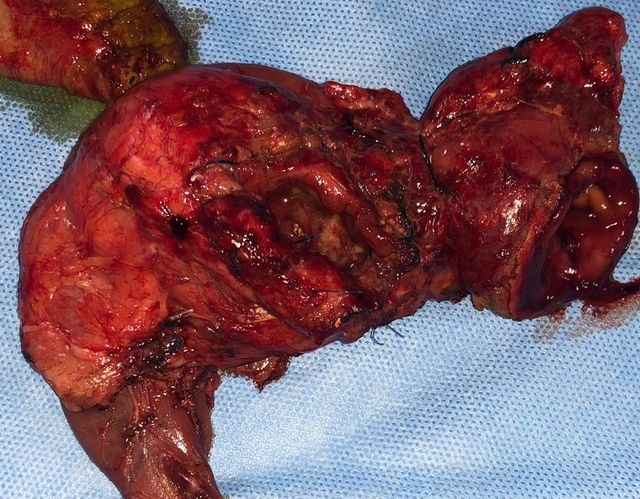

Cystic neoplasm of Pancreas

Middle aged female patient came with complaints of chronic upper abdominal pain since 6 months. The pain was mild to moderate, dull aching, non-radiating and not related to meals or defecation. It was not associated with vomiting, jaundice or abdominal lump. CT Abdomen suggested a cystic lesion in the distal body of pancreas of size 3x3 cm without communication with PD. Endoscopic Ultrasound guided Fine-needle aspiration (FNA) was performed and aspirated fluid suggested elevated CEA levels to 1168 with elevated amylase and lipase with mucin stain positive. Patient underwent laparoscopic spleen preserving distal pancreatectomy (Warshaw's technique). The resected specimen suggested mucinous cystadenoma of pancreas. The patient is asymptomatic now.